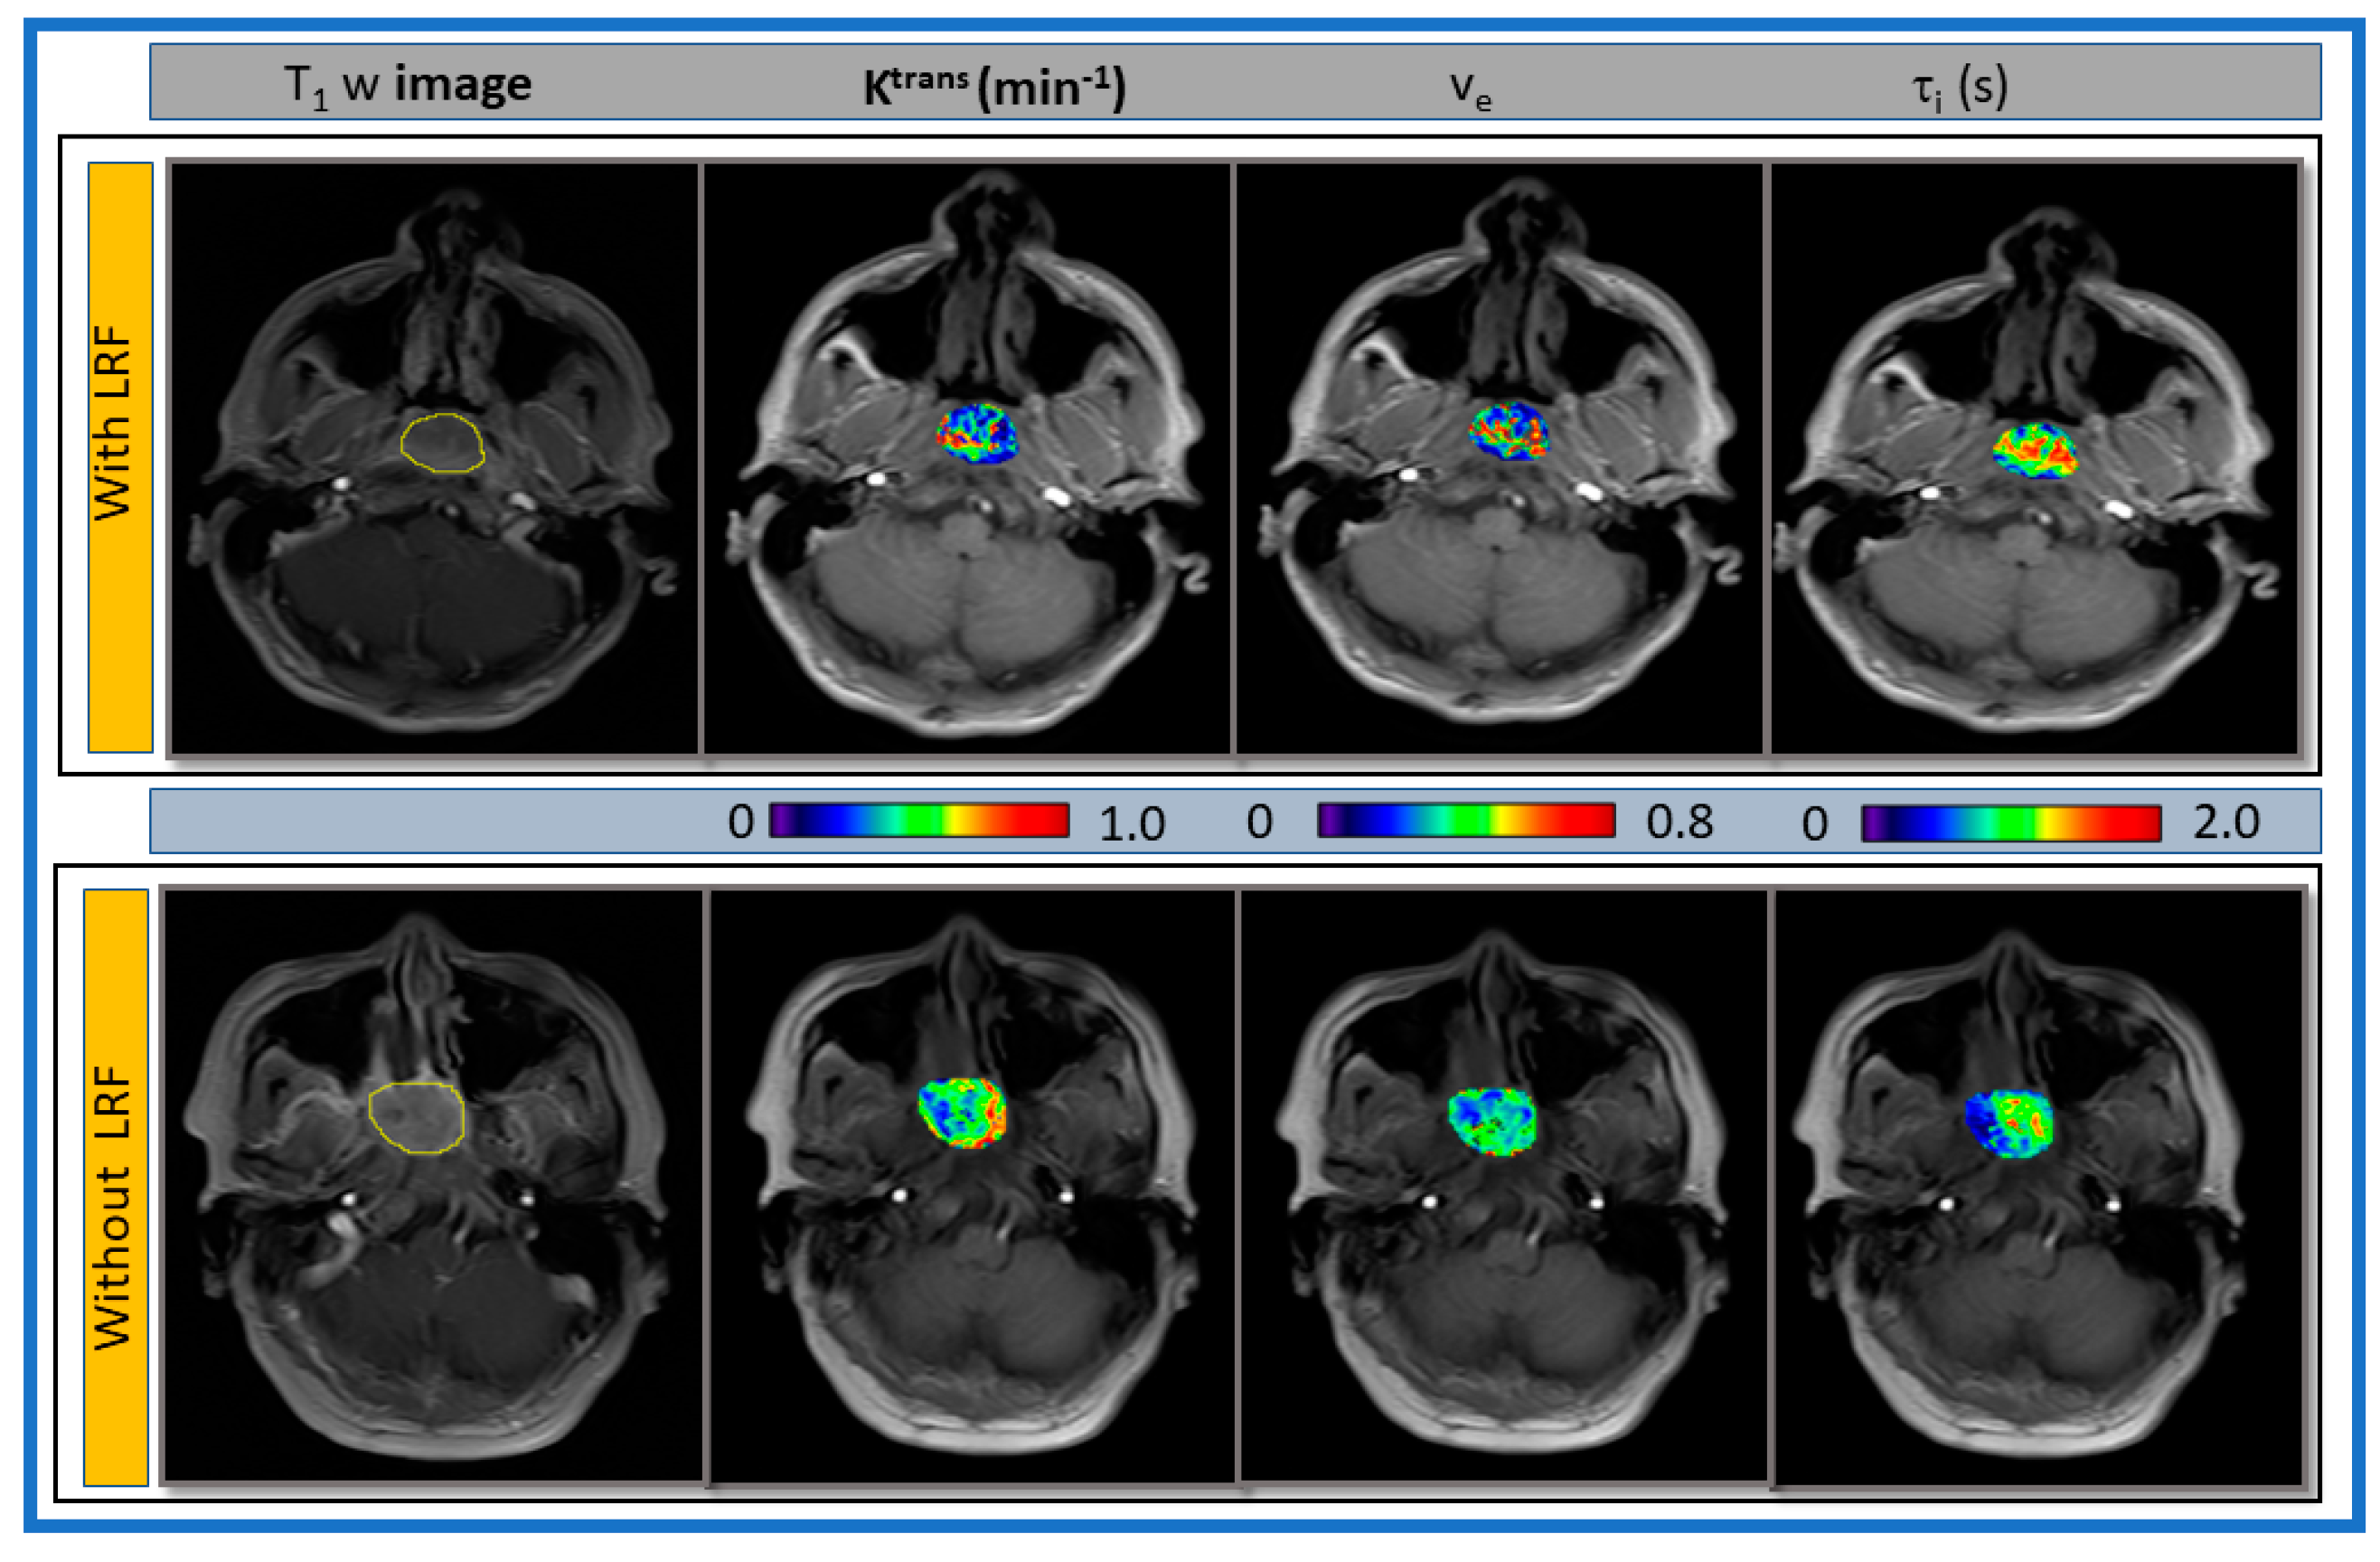

| Metric | With LRF | Without LRF | p-Value |

|---|---|---|---|

| Ktrans (min−1) | 0.29 ± 0.11 | 0.39 ± 0.16 | 0.14 |

| ve | 0.23 ± 0.13 | 0.44 ± 0.21 | 0.03 |

| τi (s) | 0.91 ± 0.15 | 0.71 ± 0.27 | 0.11 |